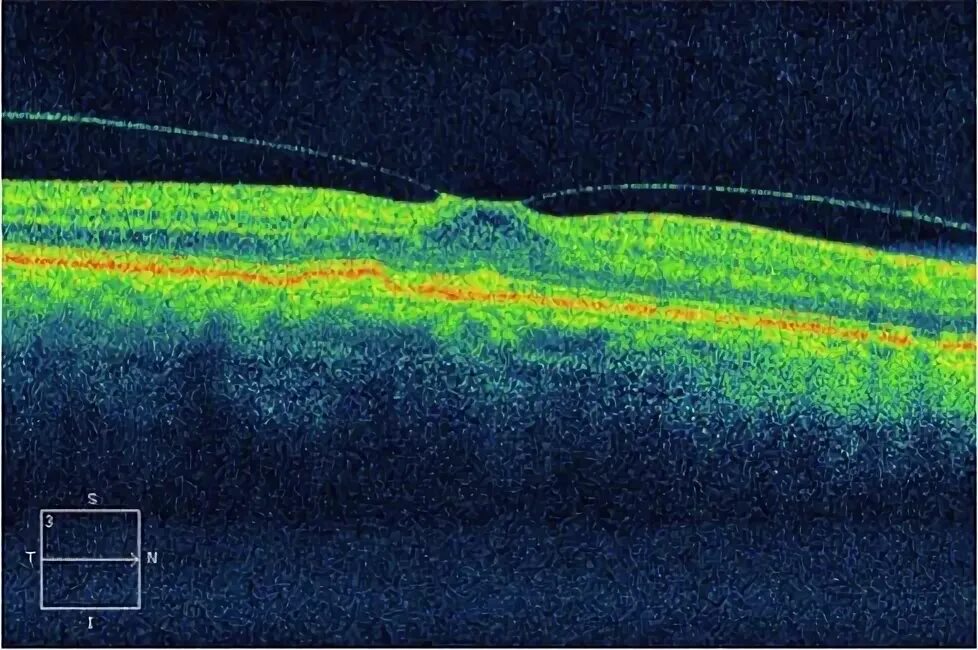

Макулярный разрыв после операции